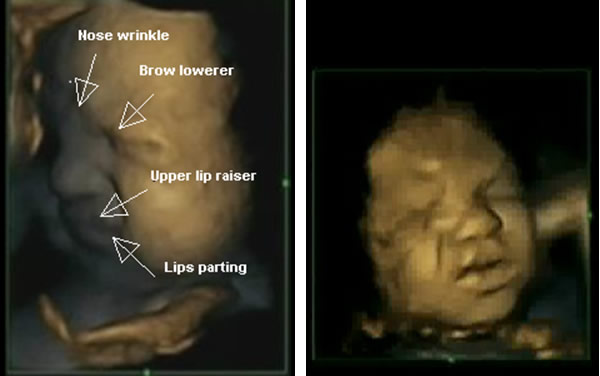

Research on fetal facial movements indicates that fetuses who are neither stimulated nor in pain are capable of coordinating their facial muscles to form a pain expression using facial muscle movements that were associated with pain expression in newborn and premature infants[8]. In this study, six facial movements were identified with combinations of four facial movements expressing painful facies (see Fig 1) as seen in premature infants[9] and relating to the core behavioural cues of infant clinical pain as assessed by the Neonatal Facial Coding System[10].

Fig. 1 Fetuses showing ‘pain’ ‘distress’ expressions